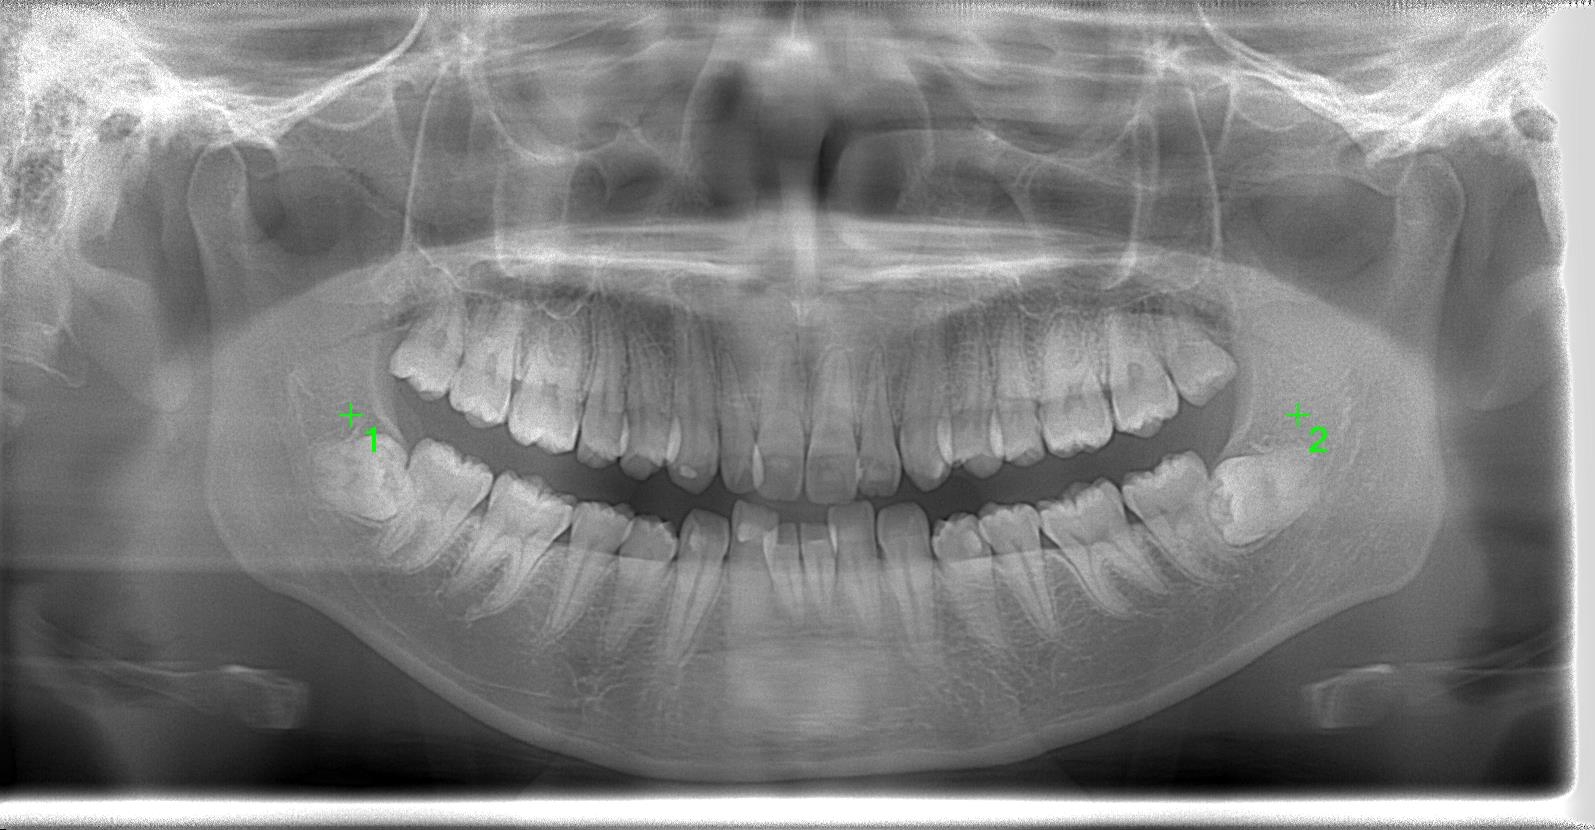

[術前パノラマレントゲン写真]

第3大臼歯を抜歯して矯正配列している症例です。